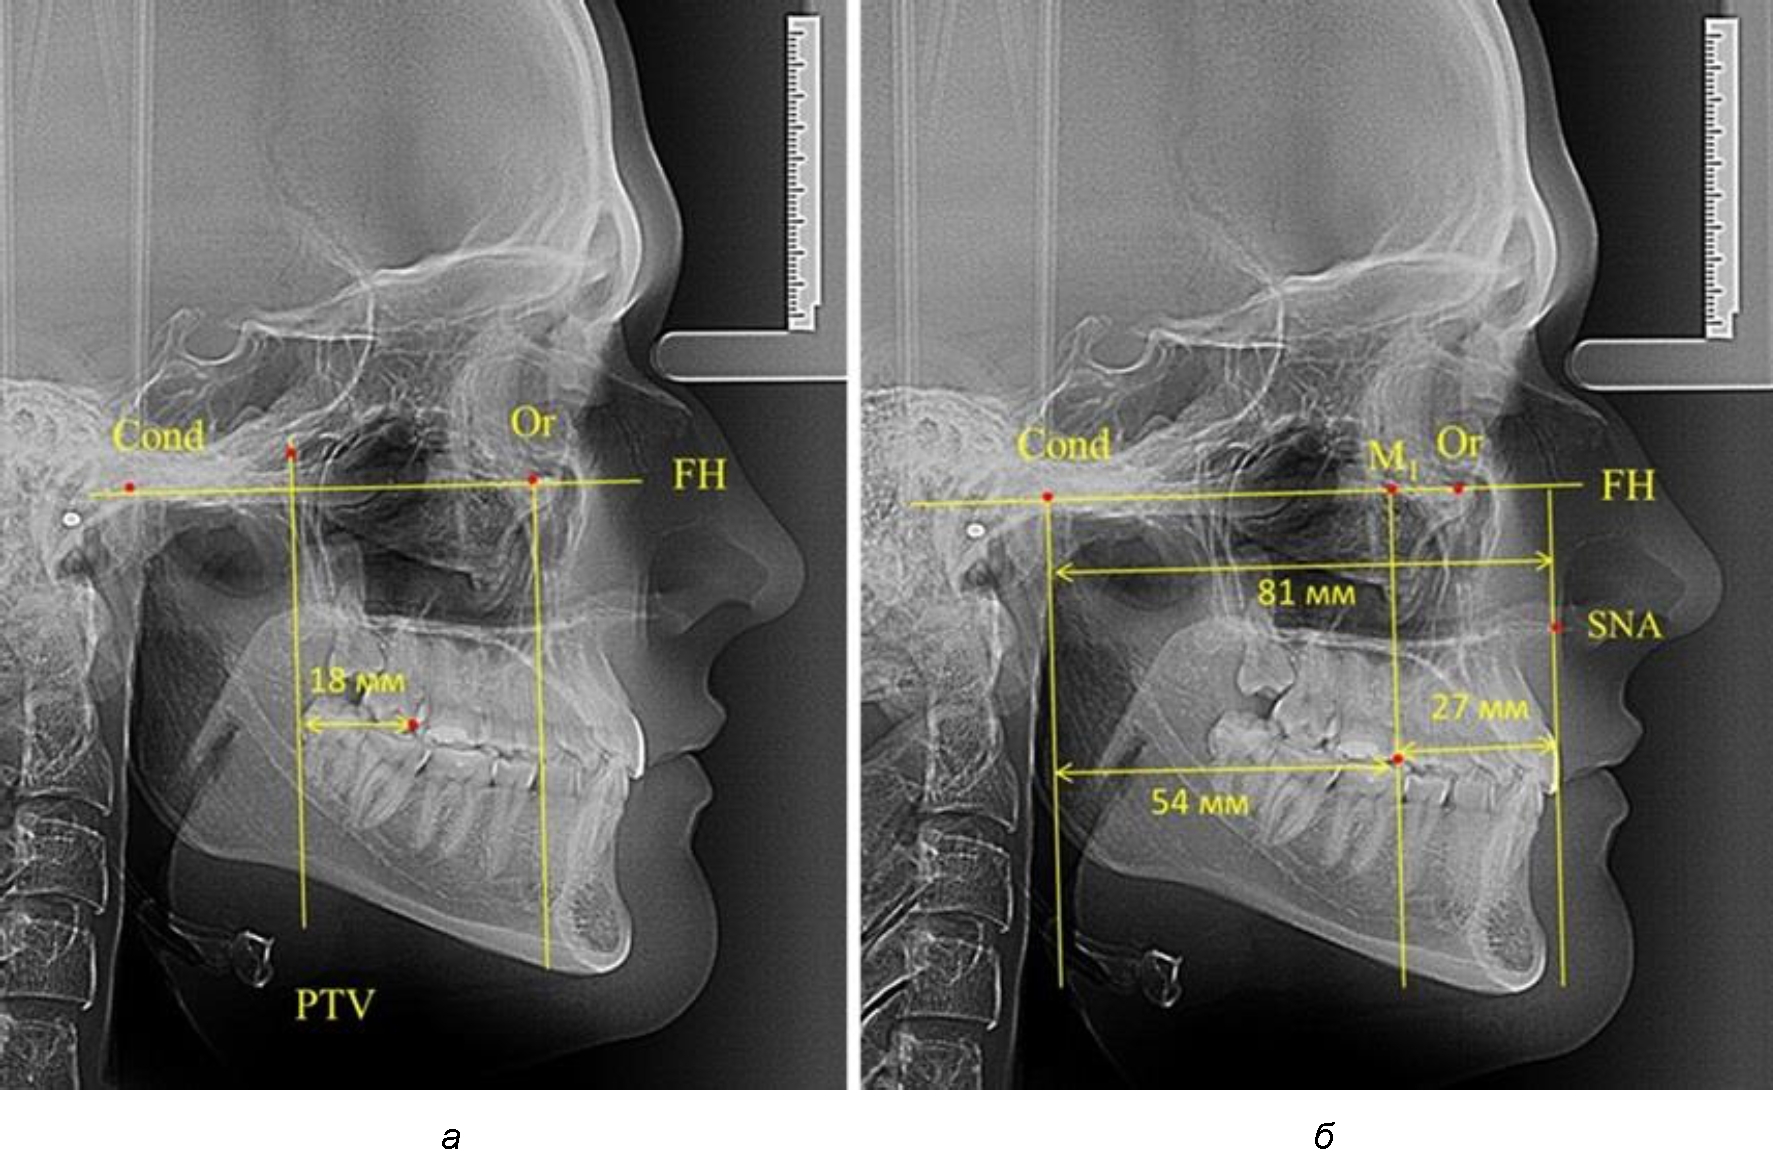

После прорезывания вторых постоянных моляров кондилярно-спинальный увеличивался до 80 мм.

Дистальная поверхность первого постоянного моляра отстояла от крыловидной вертикали на величину, составляющую около 18 мм, что, так же, как и в предыдущих периодах прикуса, было близким по значению к данным R. E. McDonald, а именно возраст, плюс 3 мм.

Обращает на себя внимание отношение глубины гнатического отдела лица к дистальному отделу, а именно к кондилярно-молярному расстоянию, которое, вне зависимости от сагиттальных размеров, составляло 1 : 1,5.

Рентгенограмма 16-летнего ребенка, с реперными линиями и анализируемыми линейными параметрами по двум используемым методам, представлена на рис. 6.

Рис. 6. Особенности положения первых моляров по R. E. McDonald (а) и по предложенному методу (б) у ребенка 16 лет